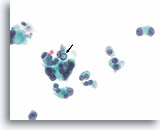

Afbeelding 23

Cellulair laesie, folliculair neoplasma kan niet worden uitgesloten (hürthlecelneoplasma vs lymfocytische thyroïditis), schildklier, ThinPrep®.

Er is een microfolliculaire groep hürthlecellen met enkele mogelijke lymfocyten aanwezig.

60X

Afbeelding 23

Cellulair laesie, folliculair neoplasma kan niet worden uitgesloten (hürthlecelneoplasma vs lymfocytische thyroïditis), schildklier, ThinPrep®.

Er is een microfolliculaire groep hürthlecellen met enkele mogelijke lymfocyten aanwezig.

60X